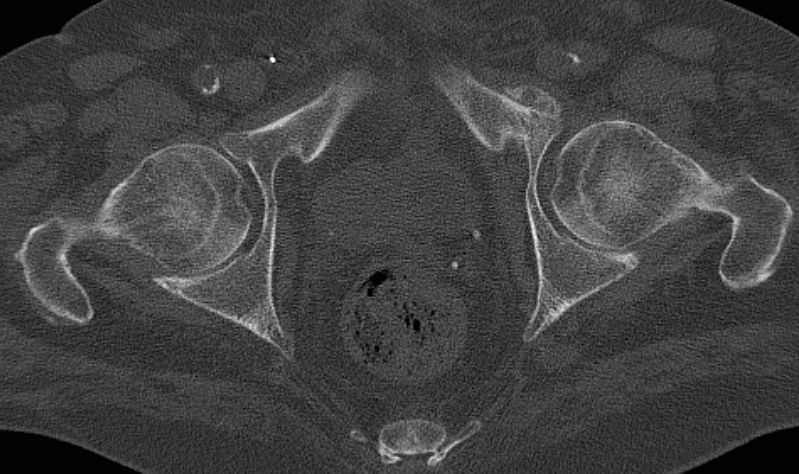

| Knochenmetastasen | 72-jähriger Patient, der vor 3 Jahren ein Harnblasen-Ca hatte: Blasenteilresektion. | Vor 2 Jahren 1. Rezidiv T1 G2: TUR-B. Vor einem Jahr 2. Rezidiv: Blasenteilresektion pT3a G3. | Vor 4 Monaten Lungenmetastastasen. Jetzt Schmerzen beim Sitzen und Belastung des linken Beins. |

Metastase Schambein links mit Kallusbildung.![]() |

Frische lytische Metastase im linken Sitzbein![]() |